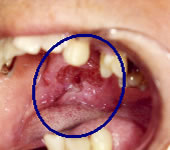

咽喉頭異常感 こんな症状があったら早めに私どもにご相談ください。 何となく喉がつかえる感じがする、痛みが続く、声がかすれる、飲み込みが悪い、むせてしまう、ダイエットしていないのに体重が減った、痰や唾液に血液が混じる…。

私どもは癌を見逃さないよう細心の注意を払っています。 ○当院における検査システム

電子内視鏡による詳細な観察 レントゲン検査、血液検査 最新式超音波診断装置による検査 必要に応じて、CT, MRI, 腫瘍シンチグラム検査 (提携病院にご紹介) 万一癌が発見された場合、 癌研究会有明病院、国立がん研究センター中央病院など高度医療機関で、迅速かつ適切な治療が開始できるようご紹介いたします。 |